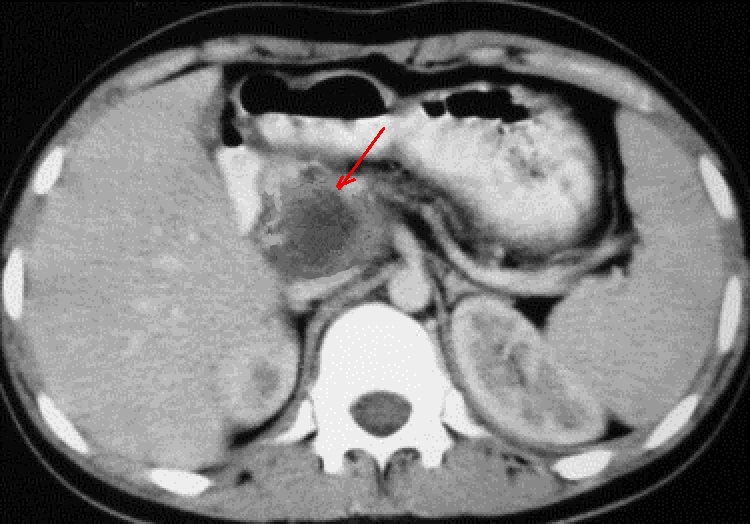

Une tumeur acinaire tres volumineuse de la tete du

pancreas avec aspect lesionnel d'une masse hypodensite non homogene

, encapsule a bord tres nette ( fleche rouge ) .

Zone de nesrose kystique se retrouve dans 1/3 de la

tumeur . Image radiologique TDM en coupe axilaire |